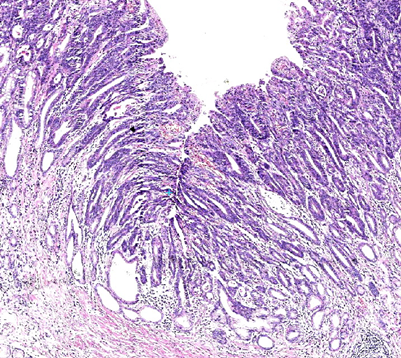

胃粘膜萎缩